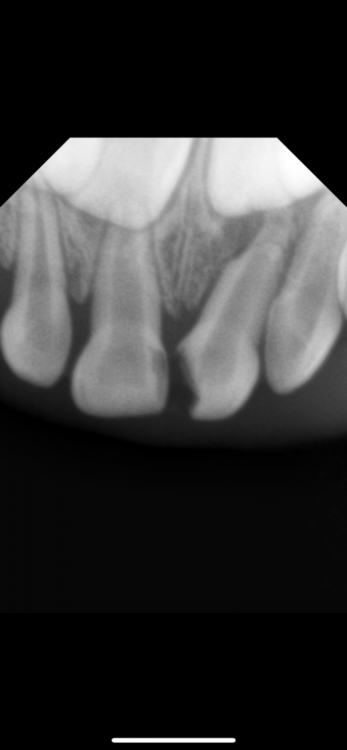

Polina21 Опубликовано 4 декабря, 2022 Поделиться Опубликовано 4 декабря, 2022 Здравствуйте!Ребенку 4года,молочный передний зуб частично разрушен. Были у стоматолога, сказали кариес,еще немного и источится до нерва. Сказали все там чистить и ставить пломбу,но делать под седацией. Хочу услышать ваше мнение судя по снимку Ссылка на комментарий

сирена Опубликовано 5 декабря, 2022 Поделиться Опубликовано 5 декабря, 2022 Правый зуб лечить, левый удалять. Там уже давно дошло всё до нерва , есть периапикальные изменения(в кости). Можно одномоментно под седацией, можно без седации, просто под местной анестезией, как будет вести себя ребёнок. Ссылка на комментарий

IvanK Опубликовано 5 декабря, 2022 Поделиться Опубликовано 5 декабря, 2022 17 часов назад, Polina21 сказал: Здравствуйте!Ребенку 4года,молочный передний зуб частично разрушен. Были у стоматолога, сказали кариес,еще немного и источится до нерва. Сказали все там чистить и ставить пломбу,но делать под седацией. Хочу услышать ваше мнение судя по снимку Здравствуйте Все зависит от ребенка, если доктор сможет договориться, то можно и без . Но С - обычно проще. Была травма переднего зуба? Делали тест на витальность? Ссылка на комментарий